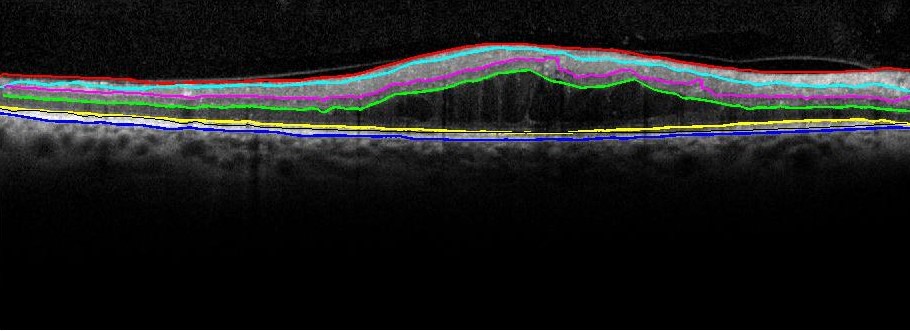

The two key steps for automated denoising and segmentation of the sub-retinal layers from OCT images are described in the following subsections. From all the OCT data image stacks each OCT image is treated as a separate standalone image while denoising and segmenting the sub-retinal surfaces. This operation of separately segmenting each image without any information regarding the adjacent images from the OCT image stack is different from the existing graph-based segmentation approaches in [16]. Once each image is denoised, 7 sub-retinal surfaces, i.e., Surface 1 to Surface 7, and 6 sub-retinal layers that are then segmented are shown in Fig. 1. The segmented sub-retinal layers extend from the inner limiting membrane (ILM, Surface 1) to the Bruch’s Membrane (BM, Surface 7) surface. The automatically segmented sub-retinal layers as shown in Fig. 1 are: the Nerve Fiber Layer (NFL, between Surface 1 and Surface 2), Inner Plexiform Layer (IPL) and Ganglion Cell Layer (GCL) combined (IPL/GCL, between Surface 2 and Surface 3), Inner Nuclear Layer and outer plexiform layer combined (INL, between Surface 3 and Surface 4), Outer Nuclear Layer (ONL, between Surface 4 and Surface 5), Photoreceptor Inner/Outer Segment (IS/OS, between Surface 5 and Surface 6) and Retinal Pigment Epithelium (RPE, between Surface 6 and Surface 7). Additionally, to analyze the average retinal thickness two more combined layers are analyzed as: the Inner layer, that combines the NFL, IPL/GCL, INL and ONL (between Surface 1 and Surface 5), and the Outer layer, that combines the IS/OS and RPE layers (between Surface 5 and Surface 7).

Figure 1: The manually segmented Sub-retinal surfaces and layers in OCT images. The 7 sub-retinal surfaces are color coded as Surface 1 (Red), Surface 2 (Cyan), Surface 3 (Pink), Surface 4 (Green), Surface 5 (Yellow), Surface 6 (Black), Surface 7 (Blue). The sub-retinal layers are: NFL, IPL/GCL, INL, ONL, IS/OS, Inner and Outer layers.